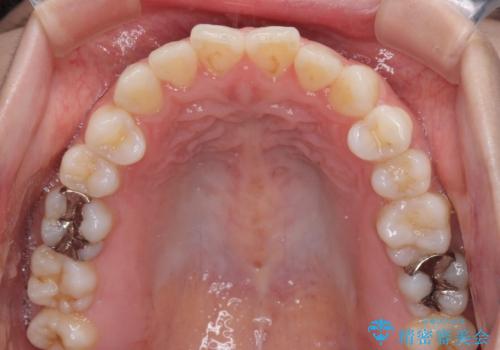

舌突出癖で口元が開いてしまう 舌トレーニングを行ったインビザライン矯正

- 前歯の上下スペースと前歯の隙間を気にして来院された患者様です。

インビザラインにより上下の前歯の隙間を閉じていくこととしました。

上下の隙間に舌が入り込むことが、すきっ歯やオープンバイトの原因であったため、舌の筋肉のトレーニングも並行して行い、後戻りの抑制を図りました。